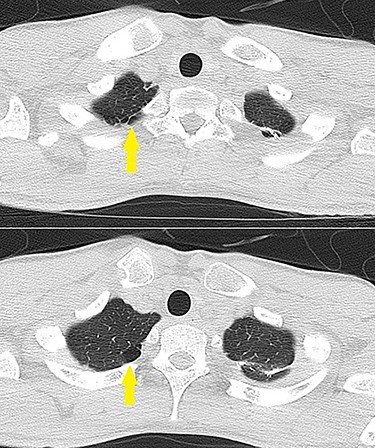

A 20-year-old man with a history of KD was diagnosed with a coronary artery aneurysm in his left anterior descending artery. His condition was controlled by antiplatelet and anticoagulant therapy, and he had no symptoms. However, coronary angiography showed progression of stenosis (Fig. 1), and his resting full-cycle ratio was 0.39; thus, CABG was planned. In addition, he had a history of two surgical procedures for left spontaneous pneumothorax. The first occurrence of the pneumothorax was a year ago, with recurrence within 6 months. The patient was tall and thin. Bullae also existed on his right lung (Fig. 2), which was possibly the cause of the new pneumothorax, because he had repeated pneumothorax in the other lung. Therefore, we planned bullectomy at the same time.

Lung CT showing bullae on the pulmonary apex of the left lung (arrows).